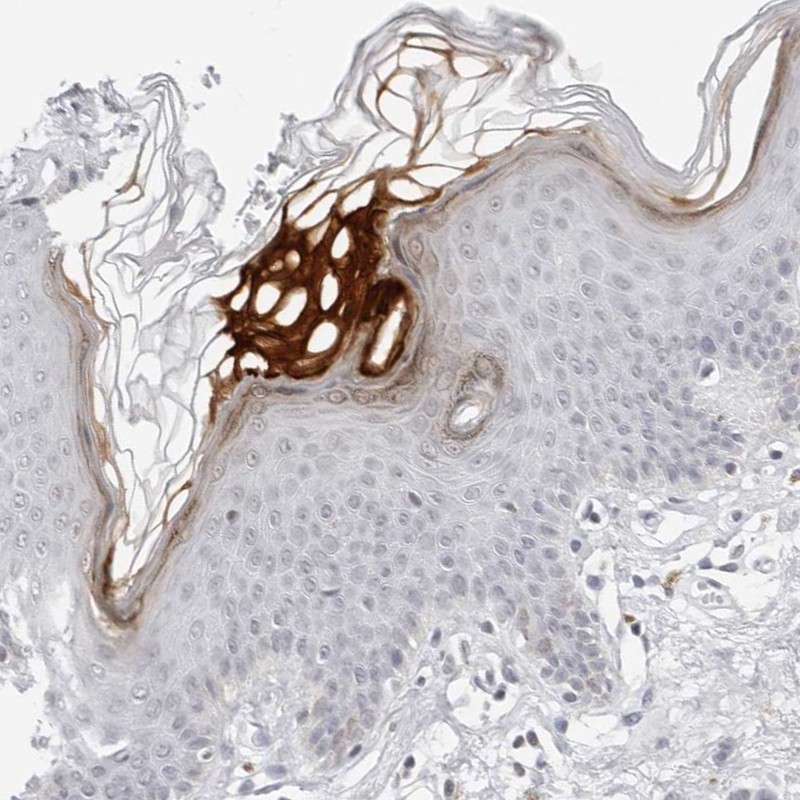

Immunohistochemical staining of human skin shows keratinocyte positivity in epidermal cells.